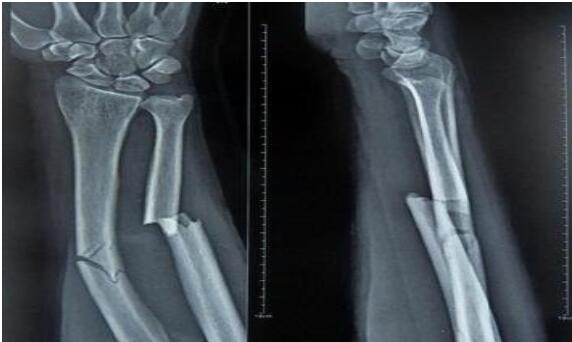

山丹接骨法是一種民間治療手段。山丹縣東樂鄉(xiāng)村民姜多明師從其父,掌握了接骨這門民間絕技。姜多明家族接骨已有上百年歷史,其父親是東樂一帶有名的中醫(yī)。改革開放前,由于農村醫(yī)療條件有限,這一技術在農村發(fā)揮了很大作用,給人民群眾減輕了不少身體上的痛苦。這項接骨技術同時也適用于給牲畜接骨。骨折愈合過程是一個高度復雜和有序的精細過程,姜多明所用的中醫(yī)傳統(tǒng)接骨法對骨折愈合起到了其他藥品不可替代的作用,效果很好。這種傳統(tǒng)的接骨方法極為簡潔,不用石膏,只用中草藥加雞蛋清,中藥主要起治療作用,蛋清起固定作用。治療周期較短,小孩子7—8天,傷勢較重的最多1月;成人根據(jù)傷勢而定,最多40—50天;牲畜所用天數(shù)根據(jù)情況而定。 2010年7月6日,山丹接骨法(民間傳統(tǒng)接骨法)被張掖市人民政府列入第二批張掖市非物質文化遺產代表性項目名錄。保護單位:張掖市山丹縣文化館。